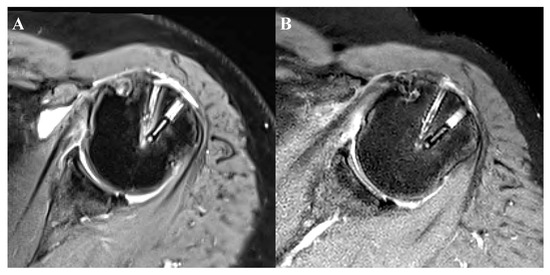

| Cyst formation, n (%) | 3 months | p-value | 6 months | p-value | ||

| Biocomposite | PEEK | Biocomposite | PEEK | |||

| Grade 0 | 8 (27.6) | 12 (41.4) | 0.085 | 7 (24.1) | 8 (27.6) | 0.581 |

| Grade 1 | 7 (24.1) | 11 (37.9) | 11 (37.9) | 11 (37.9) | ||

| Grade 2 | 6 (20.7) | 1 (3.4) | 5 (17.2) | 6 (20.7) | ||

| Grade 3 | 5 (17.2) | 4 (13.8) | 3 (10.3) | 4 (13.8) | ||

| Grade 4 | 3 (10.3) | 1 (3.4) | 3 (10.3) | - | ||

| Low grade (grade 0 or 1) | 15 (51.7) | 23 (79.3) | 0.028 * | 18 (62.1) | 19 (65.5) | 0.787 |

| High grade (grade 2, 3, or 4) | 14 (48.3) | 6 (20.7) | 11 (37.9) | 10 (34.5) | ||